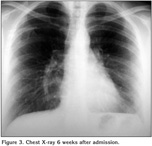

A 35-year-old woman was admitted to our hospital due to an acute left chest pain, extending to the sternum, accompanied by shortness of breath. Her pulse rate was 115/min combined with blood pressure of 105/60 mmHg. The respiratory rate was 25/min, oxygen saturation 89-91% and the axilla temperature was measured 38.8?C. Physical examination revealed reduced respiratory whispering at the left basis. Chest X-ray showed pleural effusion on the left, while the needle thoracentesis performed, attributed clear, yellowish liquid (Figure 1A). Two days later, a new chest X-ray indicated rapid deterioration and the performed chest computed tomography scan revealed extensive pleural effusion on the left (Figure 1B, Figure 2A). A chest tube was inserted and 2.300 mL of clear, yellowish liquid were drained. Six days later, a new chest computed tomography scan showed encapsulated collection at the top of the left lung, while the fever insisted with axilla temperature climbing at 39.2?C (Figure 2B).

Figure 1